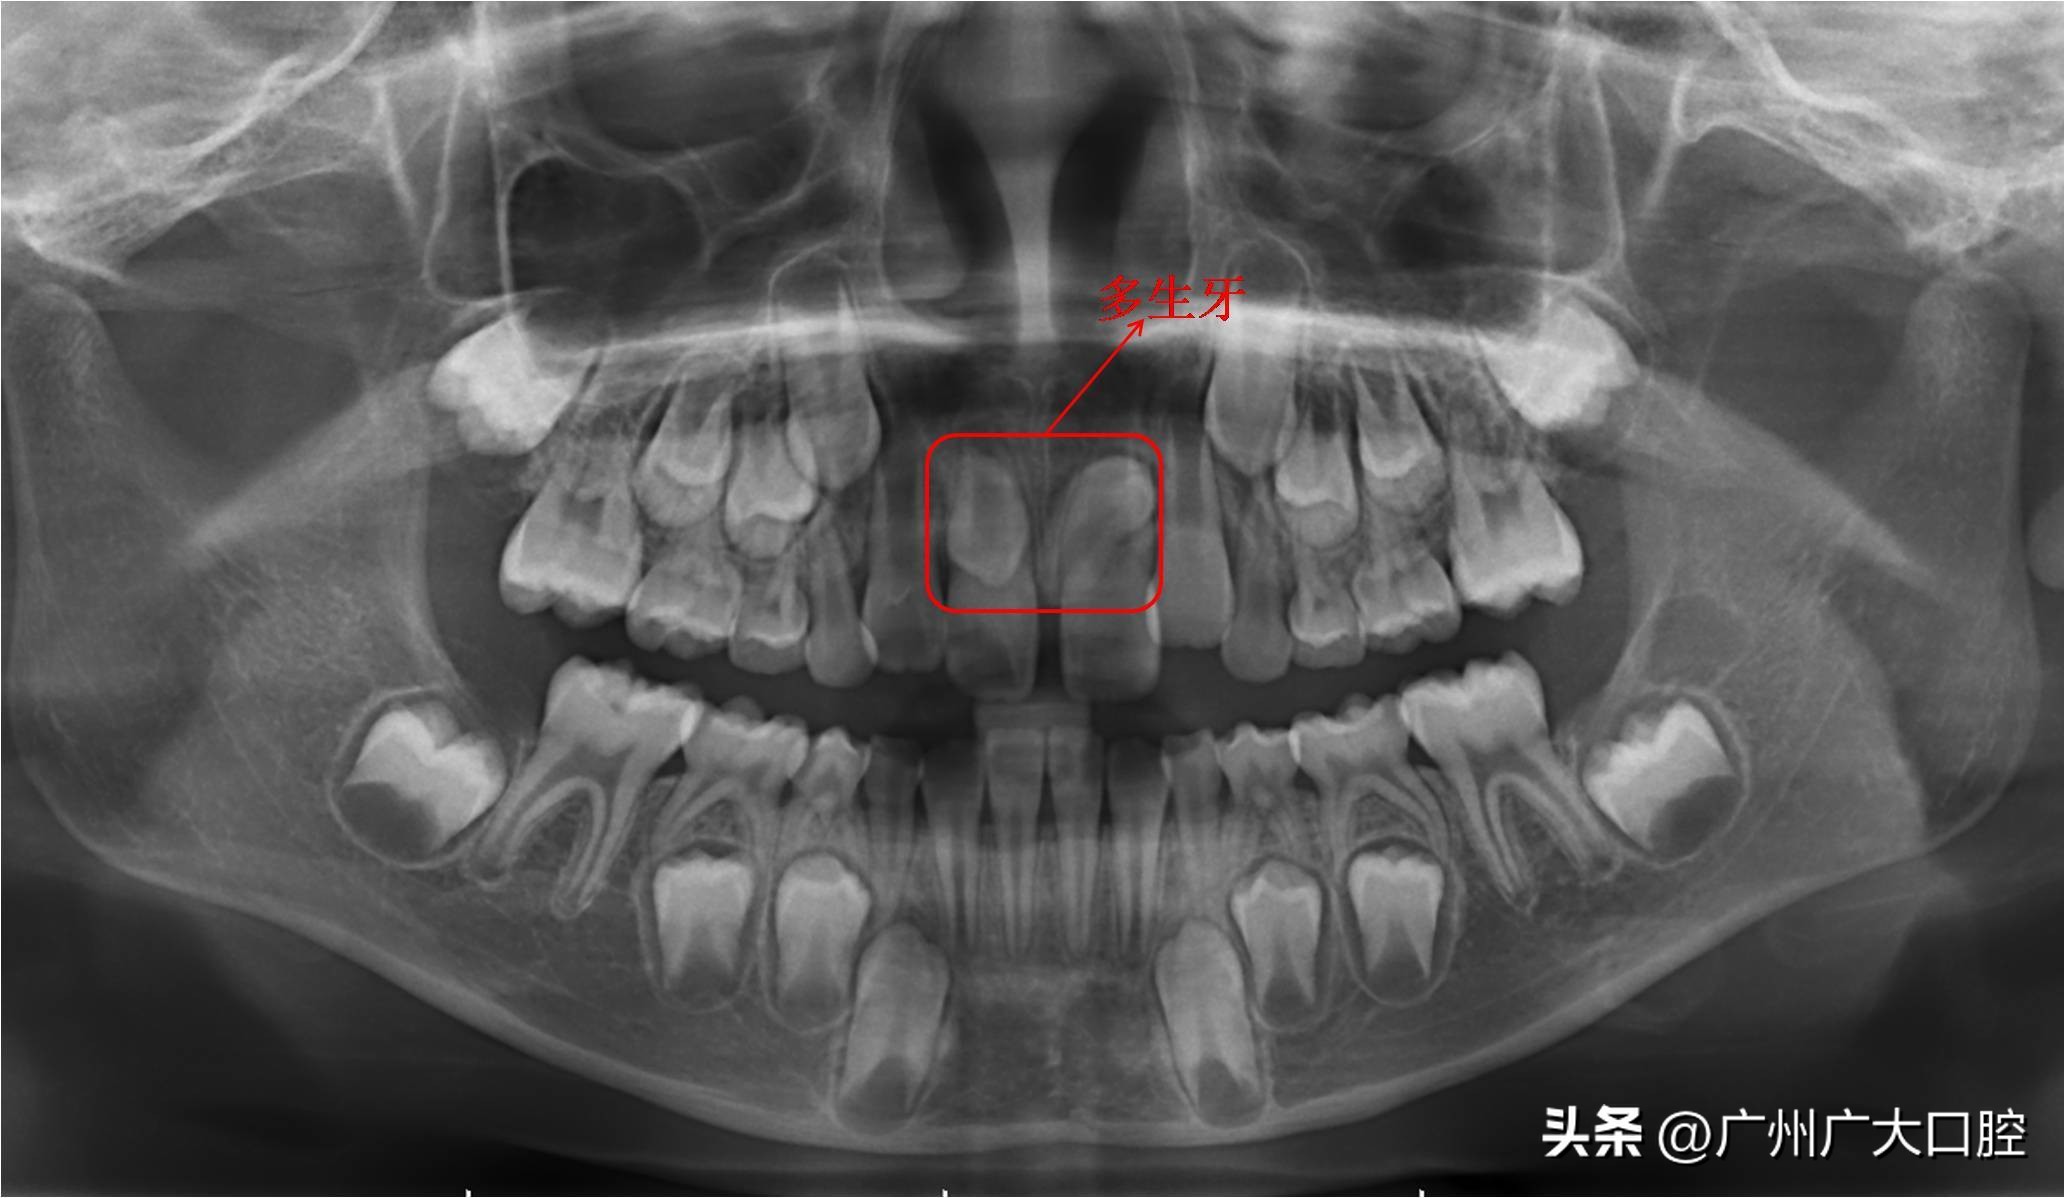

4、多生牙

多生牙就是本来不应该出现在正常牙列的多余牙齿,一般来说上颌恒牙容易出现这种问题。多生牙有可能压迫牙齿根尖,导致恒牙牙根吸收。这种情况就要拔掉多生牙,防止多生牙继续阻碍恒牙萌出,也能避免含牙囊肿。